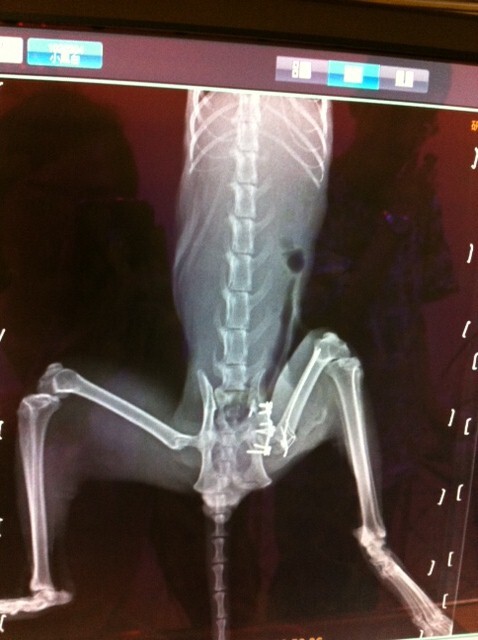

隔日送到極光動物醫院, 做了檢驗以及X光, 估計是被車撞, 檢驗的部份, 下巴脫臼, X光片顯示骨盆骨折, 骨盆腔變小, 直腸被擠到一邊, 日後恐影響無法排便, 醫師判斷自行復原不易, 需要做手術, 血檢發現貓愛滋及貓瘟, 考量到日後小黑白回到街上的生存以及手術有時間上的考量, 最後決定幫他動骨盆手術

下巴的部份醫師已先接回